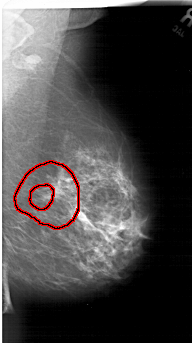

FILE: A_1485_1.RIGHT_MLO.OVERLAY

TOTAL_ABNORMALITIES 1

ABNORMALITY 1

LESION_TYPE MASS SHAPE IRREGULAR MARGINS SPICULATED

ASSESSMENT 5

SUBTLETY 2

PATHOLOGY BENIGN

TOTAL_OUTLINES 2

BOUNDARY

CORE